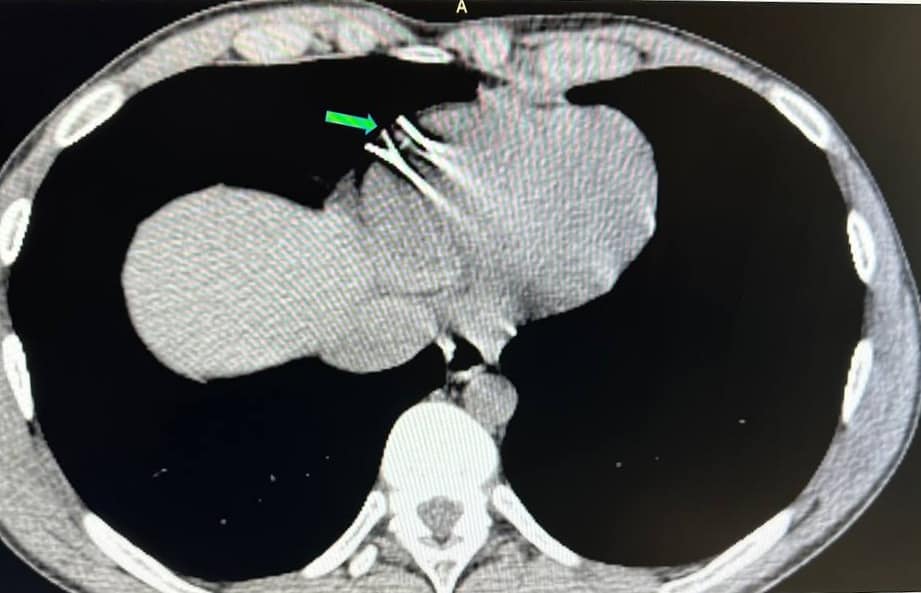

До лікарні імені Пирогова поступив 22-річний чоловік з проникаючою травмою грудної клітки. Після обстеження у нього виявили два сторонніх тіла — металеві уламки в стінці правого шлуночка серця.

7 березня у Вінницькій «Пироговці» хірурги успішно провели надскладну операцію на працюючому серці пацієнта. Операція проводилась без зупинки кровообігу через міні-доступ з використанням сучасних методів рентгеннавігації та магнітних пристроїв.